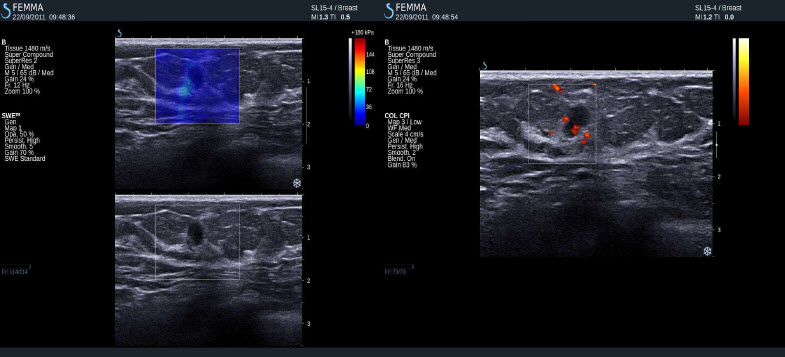

Normální tkáň prsu

Negativní výsledky elastografie / histologicky potvrzená benignita

Duktální hyperplazie, sklerozující adenoza, mikrokalcifikace